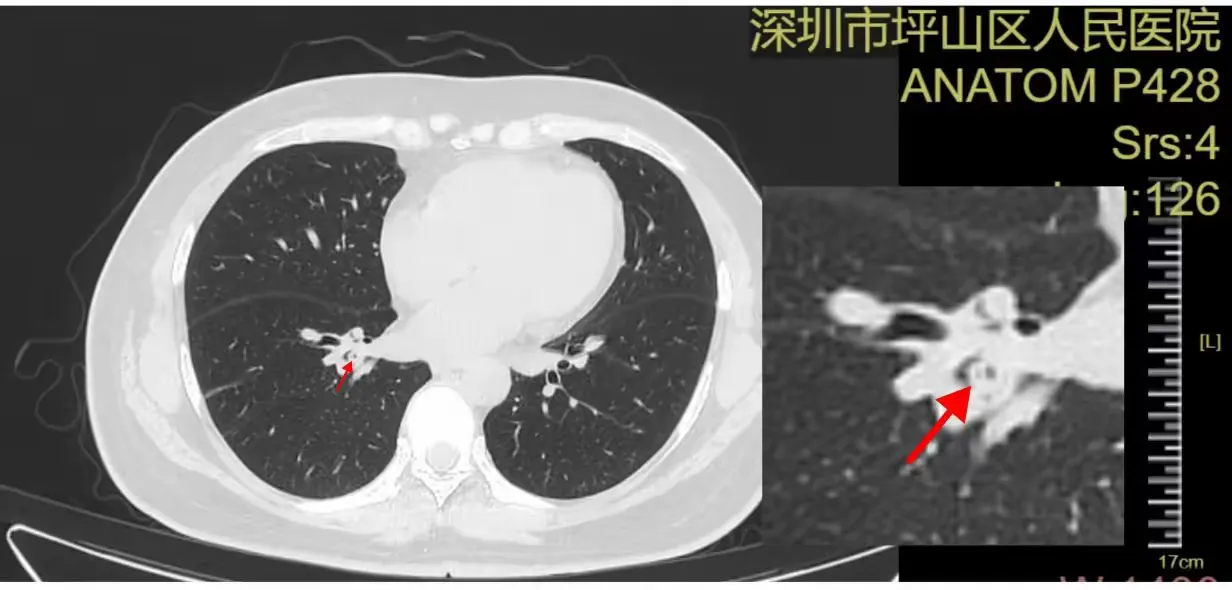

谢女士被反复咳嗽折磨了数月,尝试了多种治疗方式,却始终不见好转。于是,她来到坪山区人民医院呼吸内科门诊找到陈珍副主任医师就诊。陈珍医生详细询问病史、仔细查体,认真审阅患者胸部CT,凭借丰富的临床经验,敏锐地察觉到患者气管可能存在异常。

胸部CT就像一张“肺部地图”,而陈珍医生就是经验丰富的“侦察兵”。在看似复杂的影像中,她发现了一处不寻常的阴影——这里,就是问题的关键!当问及患者是否有呛咳史时,谢女士恍然大悟,这才回忆起数月前曾有一次剧烈呛咳,之后咳嗽便时常发作。这个发现指向了一个可能性:气道内存在异物或特殊病变。

屏幕显示,一块红色异物正紧紧地嵌在气管黏膜上,周围组织已经出现了明显的炎症反应。原来,数月前那次被患者自己都忽略了的“剧烈呛咳”,就是这块辣椒皮“闯入”气管的瞬间。它成功地“潜伏”了下来,并不断刺激气道,导致了迁延不愈的慢性咳嗽。